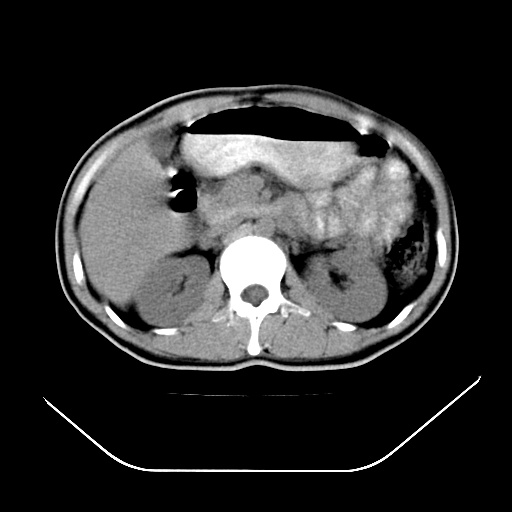

以下是引用深泽交通医院在2008-7-17 12:05:00的发言:[br]肝门淋巴结肿大;胆结石

以下是引用随光逐影在2008-7-17 17:52:00的发言:[br]1)胆囊结石。2)肝门及胰头区淋巴结肿大可能(原因不明);建议行进一步检查。

以下是引用卜一在2008-7-17 16:37:00的发言:[br]支持胆囊结石!!!至于胰头区病变——建议强化后再定论!